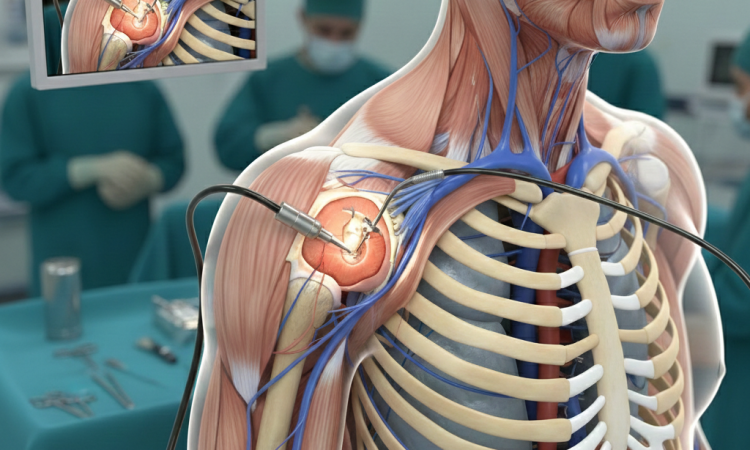

Omuz artroskopisi, eklem içindeki sorunları teşhis ve tedavi etmek için kullanılan minimal invaziv bir cerrahi...